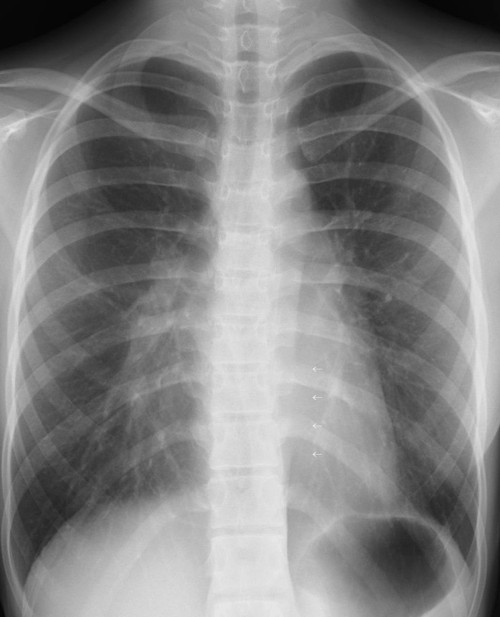

実際の読影においては、見逃しの内容に一定の順序で読む必要がある。一般的には、『胸郭→左右肺野の明るさの対比→中央陰影→気管支系→血管系→肺区域の確認→異常所見ならびに異常陰影の検出と同定→情報をもとにレントゲン診断する→病態と矛盾しないか検討する』ことが勧められている。

自分(関先生)の読影の仕方としては、関心のない領域からみることにしている。したがって肺野の所見は、出来るだけ最初の方では見ないようにしている。所見があっても無視して、いつもの読影順番でチェックをするように心がけている。

1. 胸膜や横隔膜の辺縁を追いかけていく。

2. 鎖骨、胸骨、肋骨の辺縁を確認し、肋骨に左右差がないかを確認していく。

3. 縦隔影をチェクする。右の1、2弓、左の1、2、3、4弓のラインが確認できるかどうか、位置としての異常がないかどうか、心胸比の拡大がないかどうか、心陰影に重なっているものがないかどうか、心臓の変異がないかどうかを確認する。

4. 気管・気管支、大動脈、肺動脈や縦隔線を確認していく。この際シルエットサインにも注意して診ていく。

5. そしてやっと肺や陰影を見ていくことになる。

6. 最後に、全体的に見落としがないかを再度確認しながら診なおす。この際、左右の比較をすることも大事であるが、ろっ骨と重なっている場所と重なっていない場所での濃度差にも注意して診ていく。

読影上見落としやすいレントゲン部位は、正常構造で重なりがある部分であり、そういう場、異常があるものだと思って読影することも必要である。